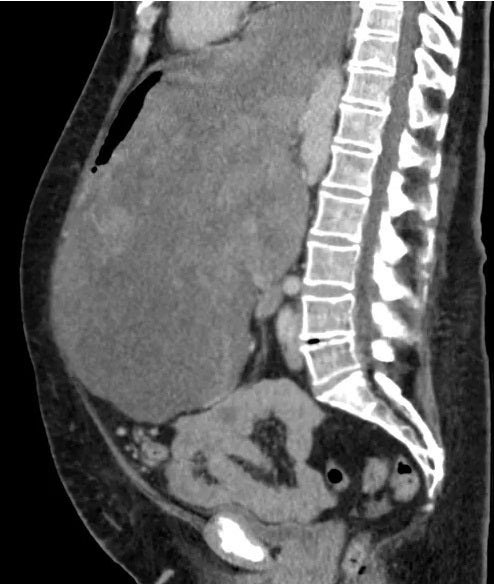

Eine riesengroße Geschwulst drückte Leber, Magen und Darm an die Bauchdecke und ragte sogar in den Brustkorb hinein. Selbst Chefarzt Hüseyin Bektas war überrascht: „Ich kenne keinen solchen Fall in Europa, aber man müsste dazu in den medizinischen Datenbanken recherchieren.“

Schließlich wurde der Patientin der 8,5-Kilo-Tumor in einer aufwendigen 6-Stunden-Operation entfernt. Die Mediziner glauben, dass die Frau den Tumor bereits ein Jahr hatte, aber nichts davon wusste. Der 65-Jährigen geht es den Umständen entsprechend gut.